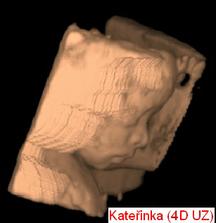

Čekání na Kateřinku... (UZ)

Čekáme holčičku - Kačenku. Dokud jsme jméno vybírali, říkali jsme jí Melounka. I.TP máme 29. 2., II.TP 2. 3. 2008. a III.TP je 13. 3. 2008.